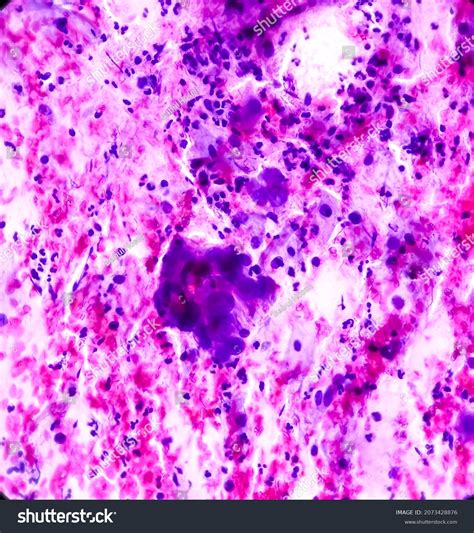

Understanding the significance of Atypical Squamous Cells (ASC) is crucial for anyone involved in healthcare, particularly those dealing with cervical cancer screening and prevention. ASC is a term used in Pap smear results to describe cells that appear abnormal but do not clearly indicate the presence of cancer. This ambiguity can be both a challenge and an opportunity for healthcare providers to take proactive measures.

Atypical Squamous Cells are cells that appear abnormal under microscopic examination but do not meet the criteria for a definitive diagnosis of cancer or a precancerous condition. These cells are often detected during a Pap smear, a routine screening test for cervical cancer. The term ASC is further categorized into two subtypes:

• ASC-US (Atypical Squamous Cells of Undetermined Significance): This category indicates that the cells are abnormal but the cause is not clear. It could be due to inflammation, infection, or a precancerous condition.

• ASC-H (Atypical Squamous Cells - Cannot Exclude High-Grade Squamous Intraepithelial Lesion): This category suggests that the cells are more likely to be associated with a high-grade precancerous condition or cancer.